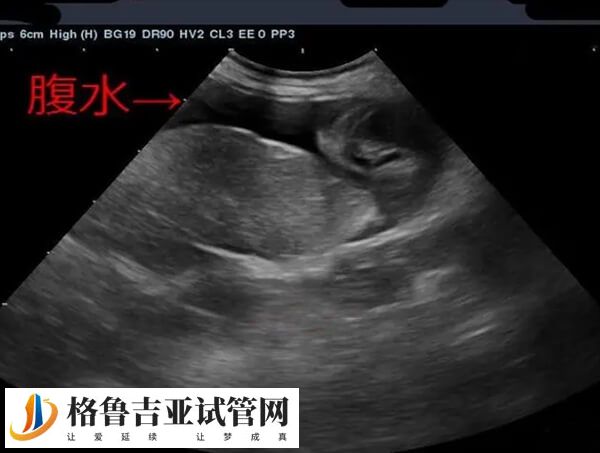

取卵后腹水症状有哪些

取卵后腹水的症状一般根据腹水量的多少和病情的轻重有所不同,通常轻度腹水的患者,可能表现为轻微的腹胀、...